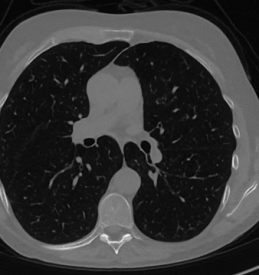

We now consider the P180,60subscript𝑃18060P_{180,60} CT protocol whose results are reported in Figure 6. In this case, the tomographic reconstruction is more challenging than in the previous experiment. The starting image xRISsubscript𝑥𝑅𝐼𝑆x_{RIS} has evident streaking artifacts and blur and some details are lost, especially in the first zoom. The artifacts are reduced in the xISsubscript𝑥𝐼𝑆x_{IS} (top right image), where some details are recovered and the edges are quite neat. The xINGsubscript𝑥𝐼𝑁𝐺x_{ING} image obtained with the proposed RISING (bottom right) is visually an excellent reconstruction. It is very similar to the xLPPsubscript𝑥𝐿𝑃𝑃x_{LPP} image, whose training, we remark, is based on more informative target images.

Refer to caption

Figure 6: Results on a test image from the Mayo data set, under the P180,60subscript𝑃18060P_{180,60} CT protocol. Top-left: xRISsubscript𝑥𝑅𝐼𝑆x_{RIS}; top-right: xISsubscript𝑥𝐼𝑆x_{IS}; bottom-left: xLPPsubscript𝑥𝐿𝑃𝑃x_{LPP}; bottom-right: xINGsubscript𝑥𝐼𝑁𝐺x_{ING}.